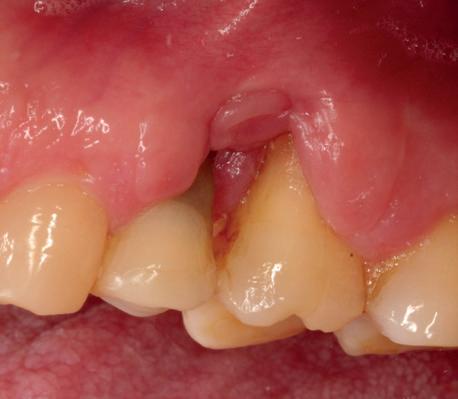

Casus

In deze casus is extractie van de 37 geïndiceerd in verband met een fistel en restpockets, zoals zichtbaar op de röntgenfoto’s (afbeelding 1). Duidelijk te zien is de forse peri-apicale ontsteking en het botverlies bij de 37, dat zowel richting buccaal als linguaal doorloopt. De 37 wordt atraumatisch verwijderd. Er is aan de linguale zijde veel bot verloren en er is sprake van een perforatie aan de buccale zijde.

Er wordt besloten om botmateriaal te plaatsen in de extractie-alveole. Vervolgens wordt het afgesloten met een titanium versterkt d-PTFE membraan (afbeelding 2). Na vier weken wordt het membraan verwijderd.

Zes maanden na extractie wordt het implantaat 37 geplaatst. Er is sprake van een goede genezing en de processushoogte en -breedte zijn behouden en opgebouwd. Ook is er zichtbaar gekeratiniseerd weefsel

gewonnen. De wond kan na het plaatsen van een healing abutment primair gesloten worden (Afbeelding 3a-3d).

In afbeeldingen 4a-c is het resultaat drie maanden na het plaatsen van het implantaat te zien. De genezing is volledig en de verwijzer kan de suprastructuur vervaardigen (afbeelding 4a-4c).

In afbeeldingen 5a-d is de implantaatkroon 37 te zien, twee jaar na plaatsing. Op de röntgenfoto is herstel van zowel corticaal als spongieus bot te zien. (De CB-CT was vervaardigd in verband met implantologische indicatie in het naastliggende gebied).

Deze casus illustreert dat er op een voorspelbare manier een ridge preservation procedure uitgevoerd kan worden met een d-PTFE membraan en er daarna voorspelbaar geïmplanteerd kan worden.